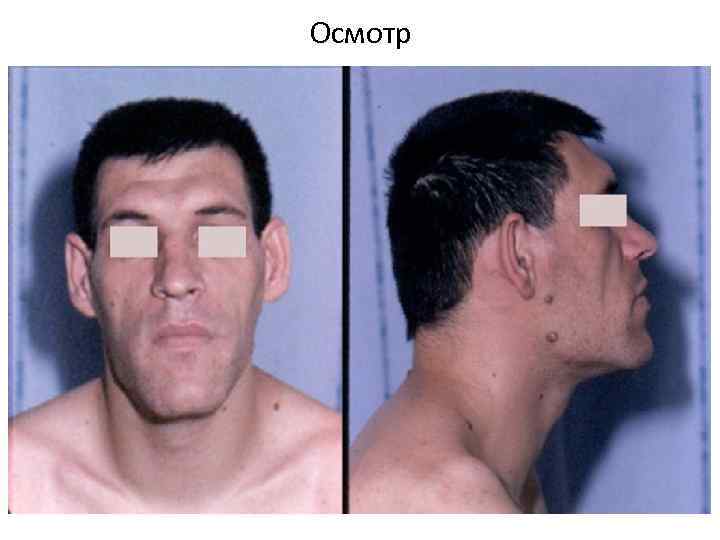

Осмотр